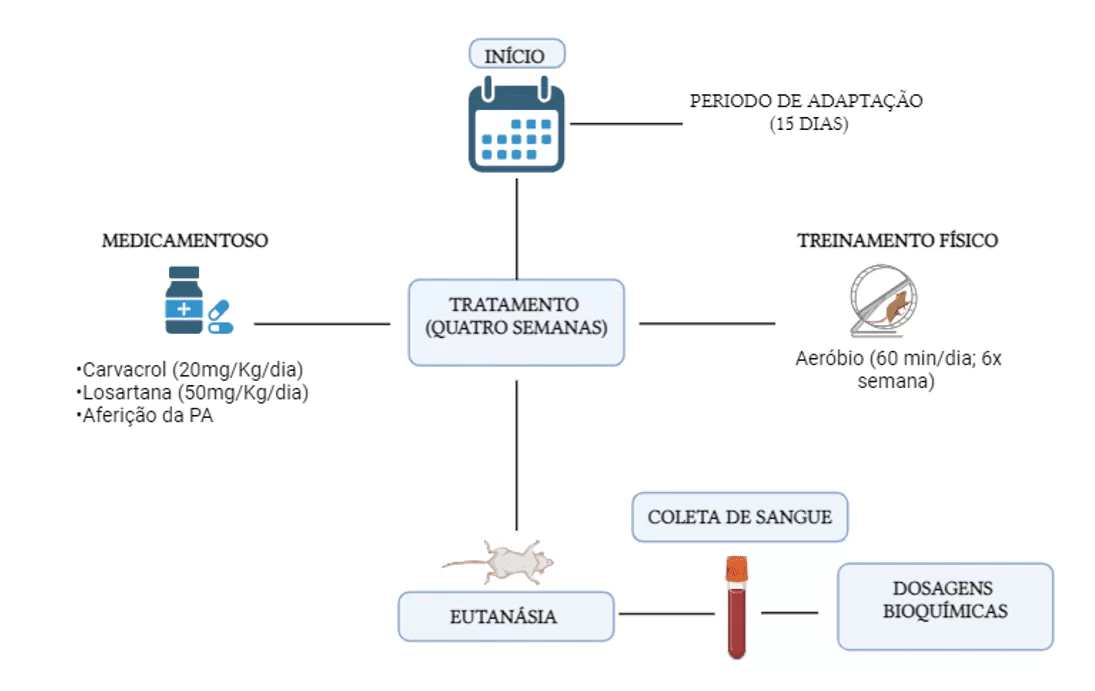

Efeito anti-hipertensivo do carvacrol envolve redução dos níveis séricos da enzima conversora de angiotensina em ratos submetidos ao treinamento físico aeróbio

Introdução: O presente estudo foi realizado para investigar os efeitos do carvacrol sobre parâmetros hemodinâmicos, lipídicos e inibição